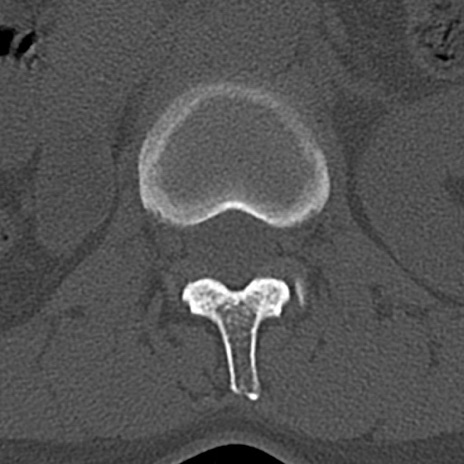

【整形】TIPS症例4 腰椎CT(横断像)

腰椎CT

横断像と矢状断像